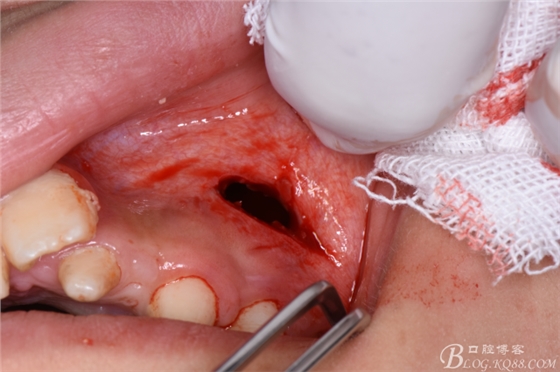

圖7.在24根尖區(qū)的前庭溝黏膜處垂直進(jìn)刀

圖8.做凸面朝向齦方的弧形切口

圖9.翻瓣、暴露出骨面